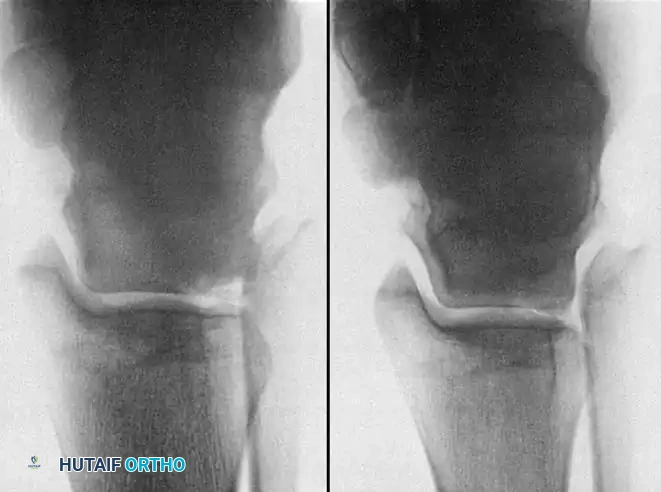

Imaging and Classification

While the Berndt and Harty radiographic classification (Stages I-IV) is historically significant, MRI is the current gold standard for evaluating the size, depth, and stability of the cartilage cap, as well as the presence of subchondral cysts.

Fig. 14: Advanced imaging modalities (CT and MRI) detailing the extent of subchondral bone involvement and cystic changes in OLTs.